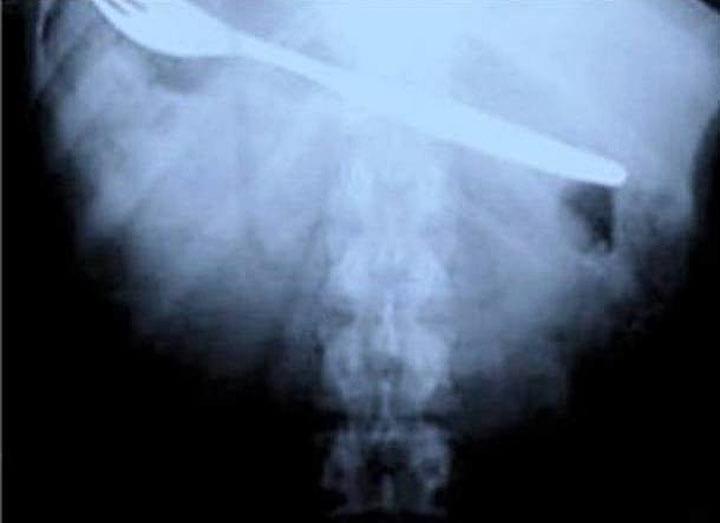

3. Вот что значит плохой день. Этот человек случайно проглотил таракана и попытался достать его вилкой. Как видно, случайно проглотил и вилку…